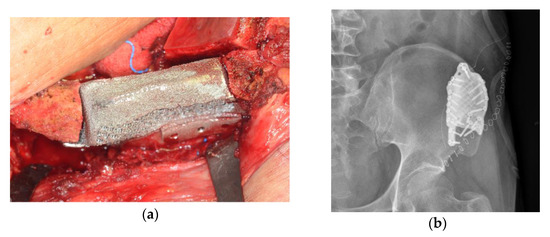

Conservative Treatment of Avulsion Fracture